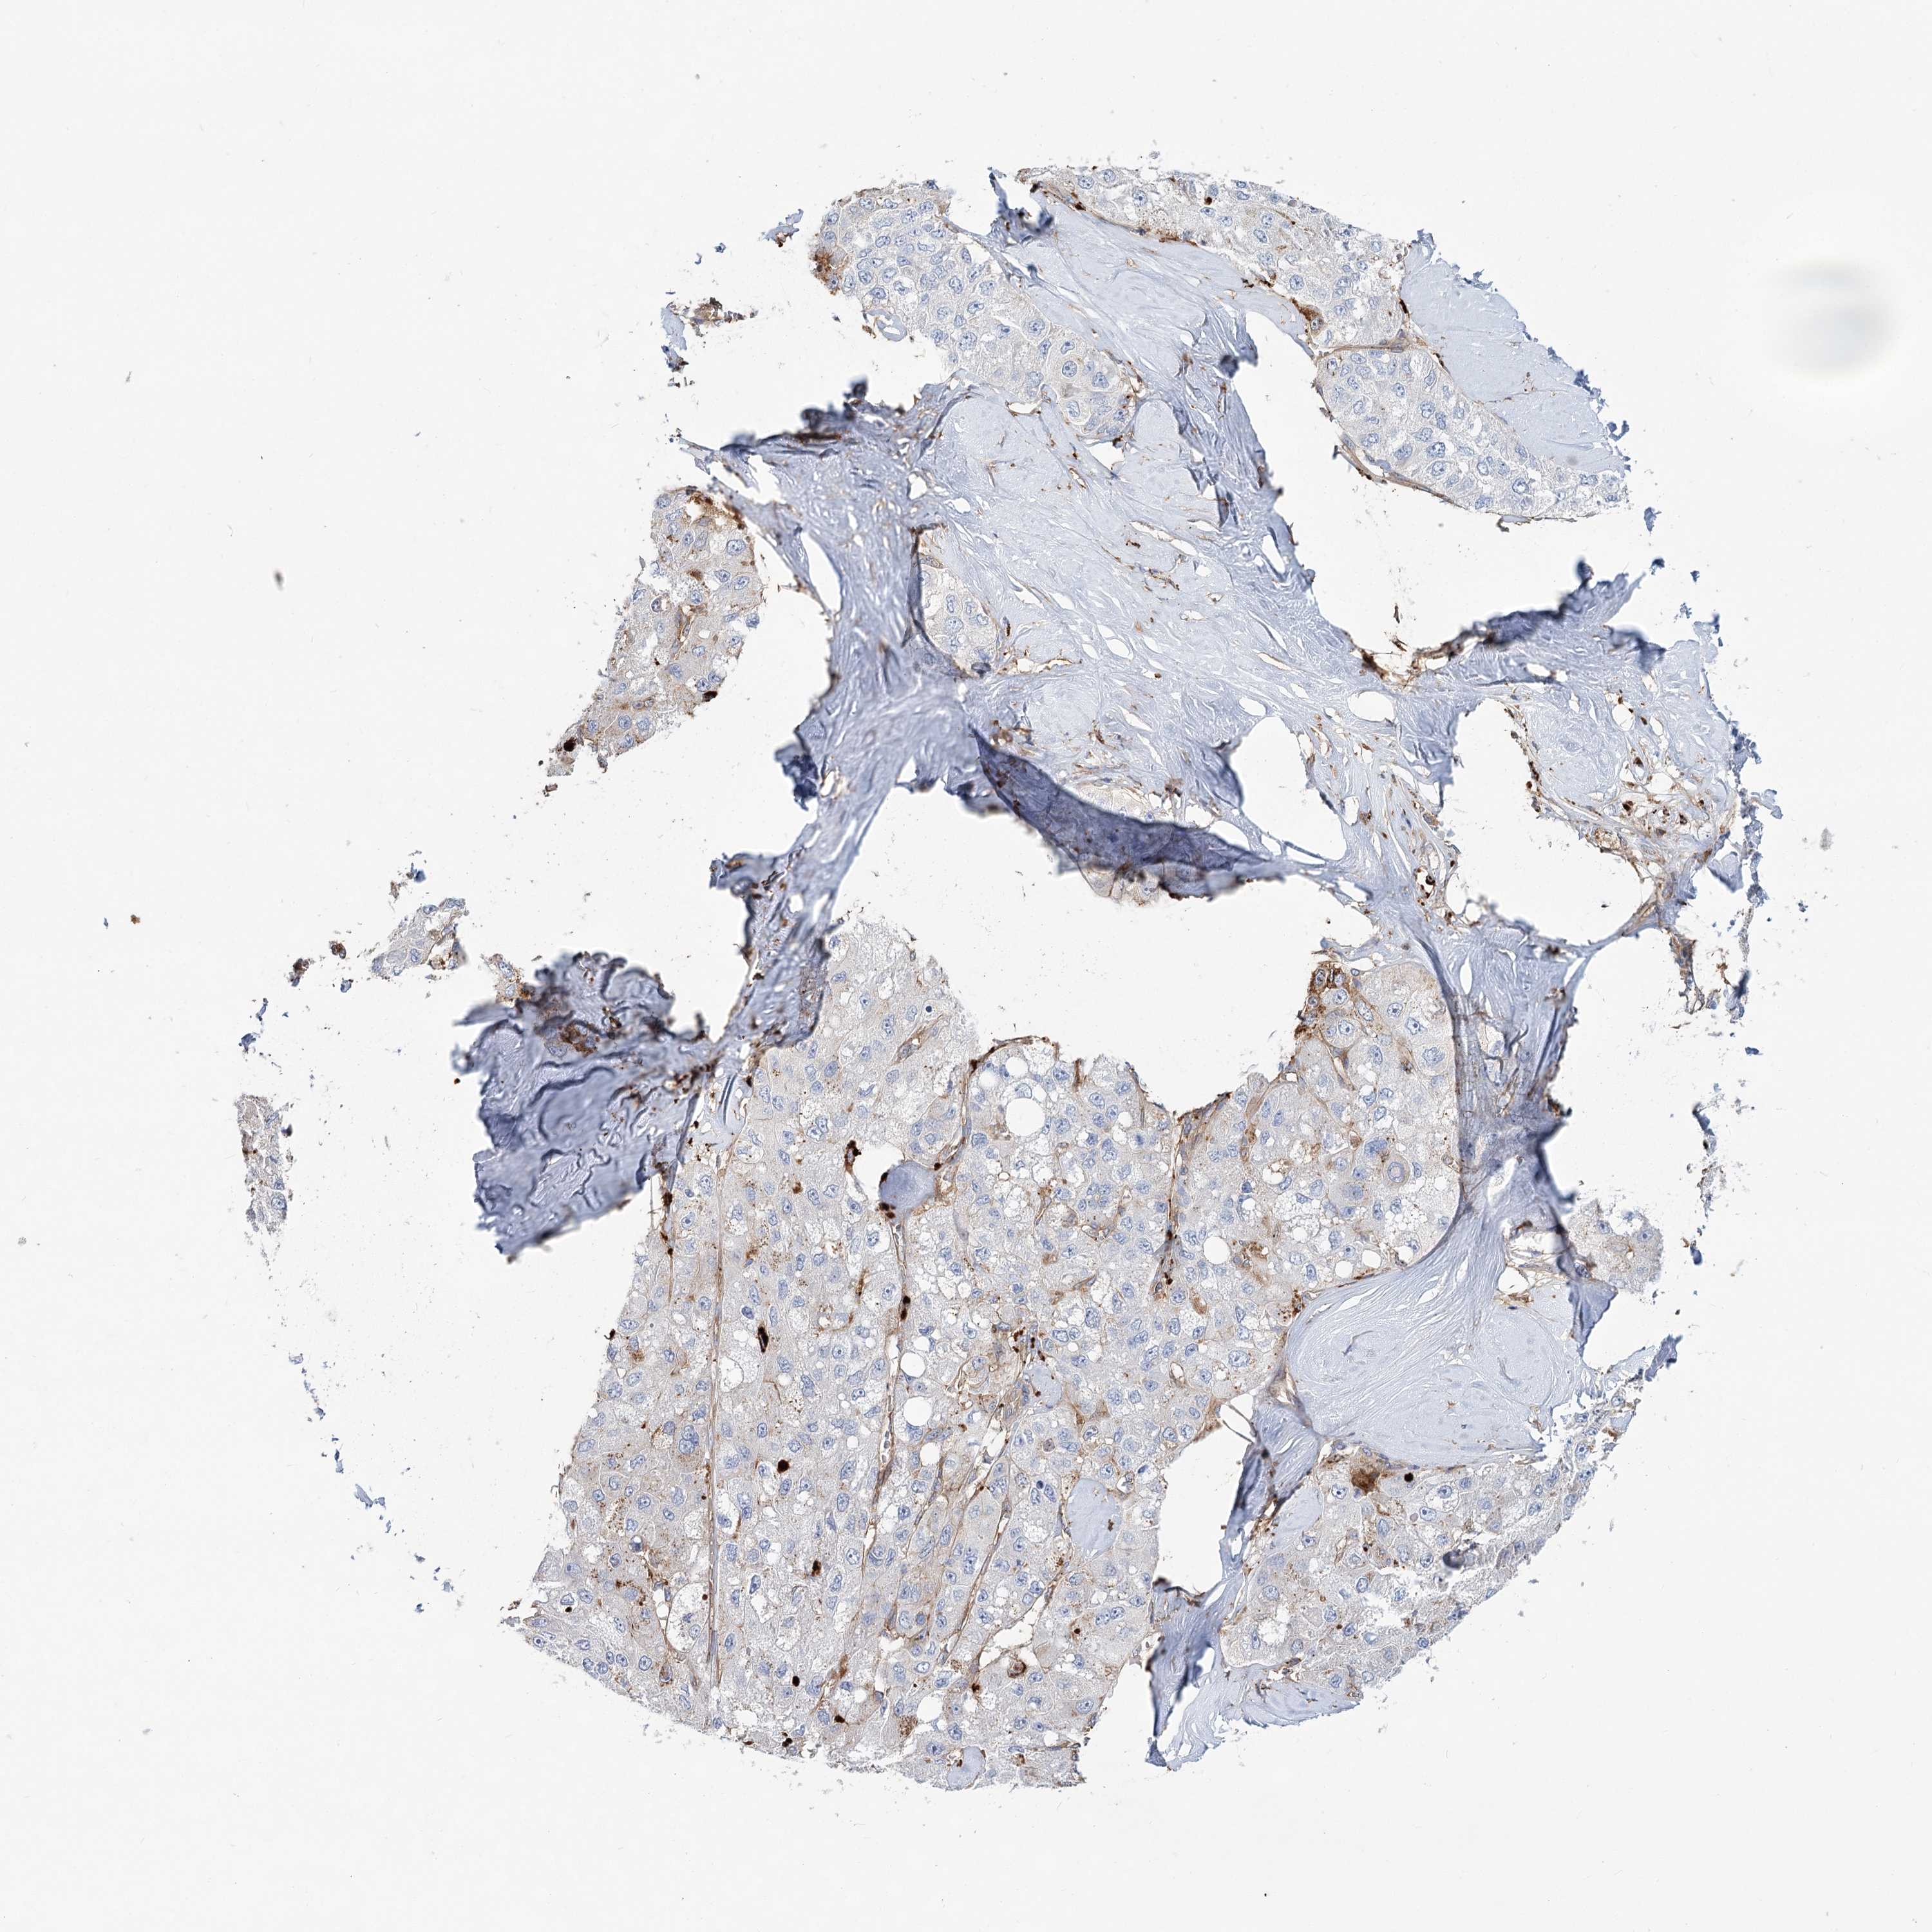

LIVER CANCER - Protein expressioni

A mouse-over function shows sample information and annotation data. Click on an image to view it in a full screen mode. Samples can be filtered based on level of antibody staining by selecting one or several of the following categories: high, medium, low and not detected. The assay and annotation is described here.

Antibody stainingi

Antibody staining in the annotated cell types in the current human tissue is reported as not detected, low, medium, or high, based on conventional immunohistochemistry profiling in selected tissues. This score is based on the combination of the staining intensity and fraction of stained cells.

Each image is clickable and will lead to virtual microscopy that enables deeper exploration of all samples and also displays staining intensity scores, fraction scores and subcellular localization as well as patient and tissue information for each sample.

Antibody HPA036322

Antibody HPA036323

Staining

High

Medium

Low

Not detected

Intensity

Strong

Moderate

Weak

Negative

Quantity

>75%

75%-25%

<25%

None

Location

Nuclear

Cytoplasmic/membranous

Cytoplasmic/membranous,nuclear

Cholangiocarcinoma

Carcinoma, Hepatocellular, NOS